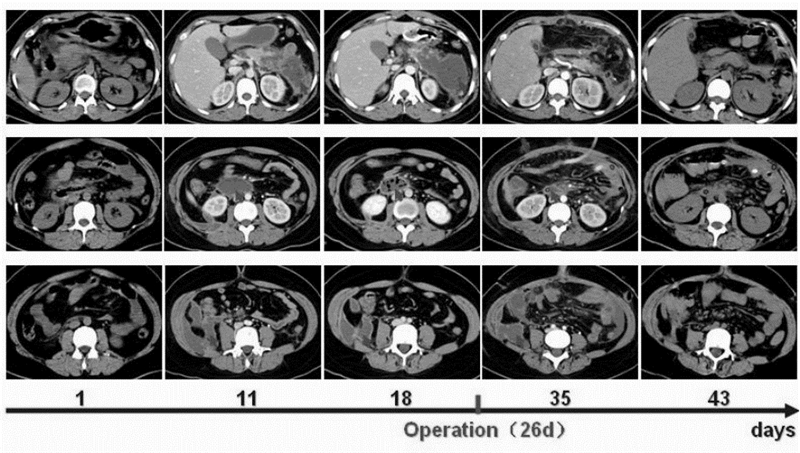

经适当补液、抑酸、抑酶及抗炎治疗后,患者病情趋于稳定,但胰腺及胰周组织病理变化进展迅速(图 1)。2周后,CT提示胰头及胰尾部大面积坏死,胰周大量积液伴右结肠旁沟、脾窝、肠系膜根部有气体分布。同时患者出现持续高热,广谱抗生素不能控制。临床考虑患者已处于胰腺感染性坏死期,遂于发病第26天行手术治疗。术中发现胰周及结肠旁沟大量脓血性液体积聚,胰腺水肿明显并伴有大面积脂肪组织坏死。而且胃小弯及十二指肠降部发现两个穿孔(图 2),同时远端胃被大量纤维组织包裹,遂给予充分暴露清创后单纯缝合各穿孔,并分别进行胃、胆囊、十二指肠及空肠造口置管以达到胰周减压及实施肠内营养的目的(图 3)。术后,在有效的腹外脓腔引流及肠内营养支持下,患者病情逐步好转,胰周及后腹膜脓腔逐渐变小并消失(图 1)。但是术后1个月,患者食管起始部及胃流出道狭窄。暂时给予患者全肠内营养并等待消化道重建术(见图 4)。

胰周大量液体积聚伴脾窝(第1行)、肠系膜根部(第2行) 及右结肠旁沟(第3行) 气体分布,发病18d时尤甚明显(红色 箭头);手术及术后有效的引流使得胰周脓腔逐步缩小 图 1 患者胰腺及胰周坏死合并感染经手术治疗的转归